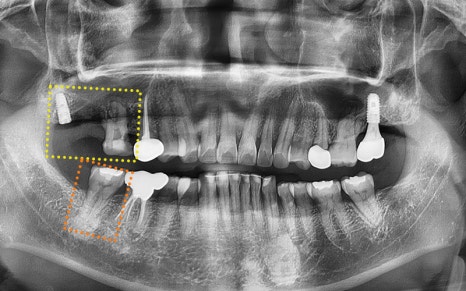

✅ 엑스레이로 본 문제점

그리고 엑스레이와 CT 사진을 촬영해

구강 내 상황을 정밀하게 체크해보았는데요.

엑스레이를 보시더니 환자분께서도

제가 봐도 너무 뒤쪽에 심긴 것 같다는

말씀을 해주셨답니다.

확인 결과, 상악동 거상술을

두 차례 시도했지만 실패했고,

결국 사랑니 위치처럼

뒤쪽에 임플란트가 식립된 상태였습니다.

임플란트 자체는 골유착이 잘 되어 있었지만,

명확한 위치가 아니어서

보철물 제작이 매우 불리한 상황이었답니다...!

게다가 앞쪽에 있는 신경치료 중인 치아는